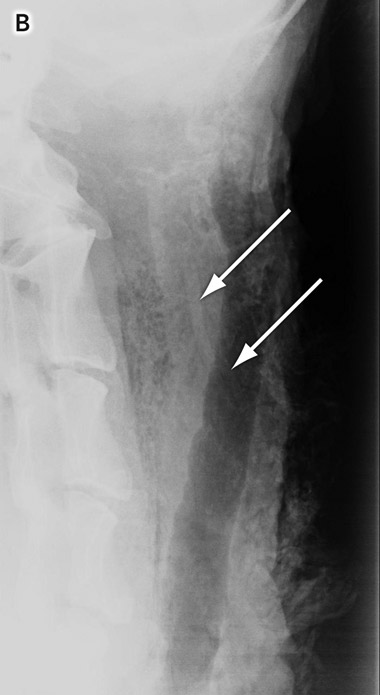

A total of 14 films (10 containing bones and four without bones, as controls) were taken and stored on removable hardware. A DICOM Editor was used to convert the images into digital images in JPEG (Joint Photographic Experts Group) format, with the standard compression defined in the Java Image I/O Tools library (a system that produces minimal loss in image quality) (Box 2, B).

2 Placement of fishbones in the specimen

![]() B: Radiographic image showing fish bones (arrows) in the soft tissue of the aerodigestive tract. |